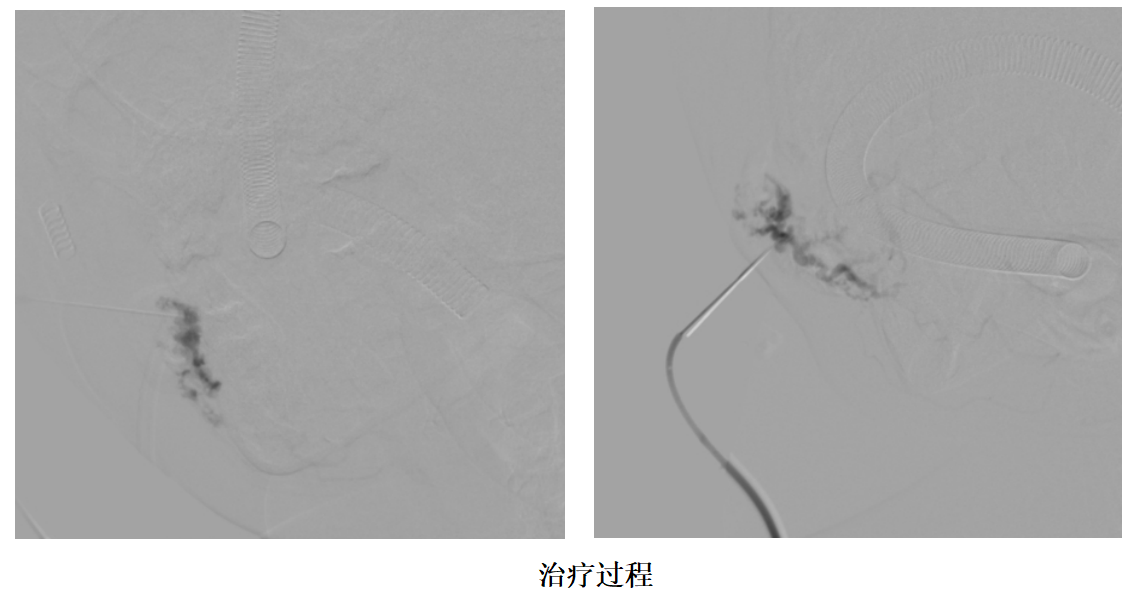

二、治疗过程

按照手术排期,1个月后,患儿来门诊做好核酸,术前检查后入院,第二天就安排入介入室行介入治疗。孩子全麻下,很顺利的进行了动脉造影、药物灌注、影像引导下硬化治疗等一系列介入手术治疗,术后第一天就平安回家了。因为患儿病灶部位在口腔部且病灶部位相对较大,在确保安全、美观的基础上对患儿进行疗程化治疗。